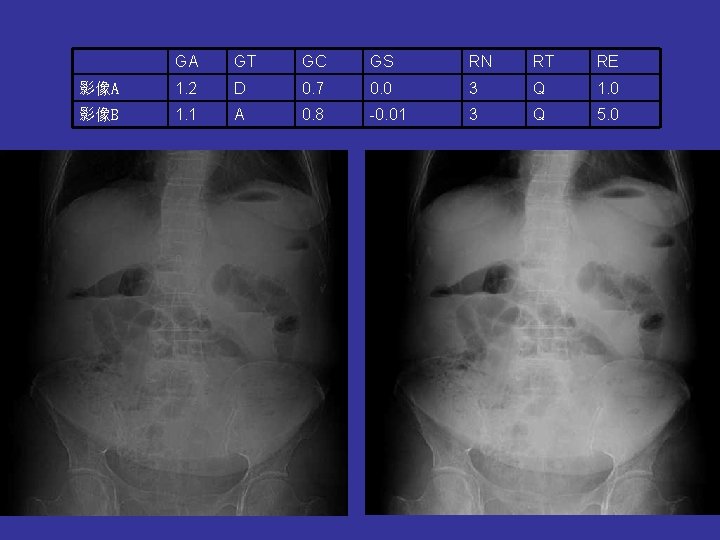

GA GT GC GS RN RT RE 影像A 1. 2 D 0. 7 0. 0 3 Q 1. 0 影像B 1. 1 A 0. 8 -0. 01 3 Q 5. 0